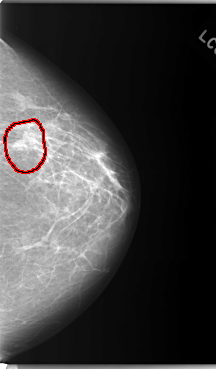

FILE: C_0103_1.LEFT_CC.OVERLAY

TOTAL_ABNORMALITIES 1

ABNORMALITY 1

LESION_TYPE MASS SHAPE IRREGULAR MARGINS ILL_DEFINED

ASSESSMENT 5

SUBTLETY 4

PATHOLOGY MALIGNANT

TOTAL_OUTLINES 1

BOUNDARY